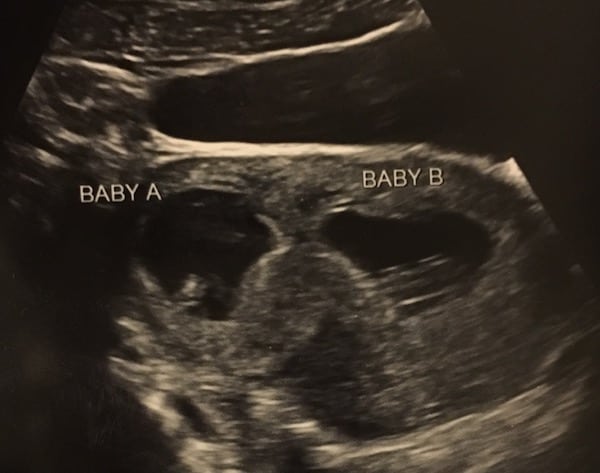

REMINDER: Don’t forget to take a belly shot! 8 week sonogram

Ultrasound Photos – 8 Week Sonogram

8 week sonogra